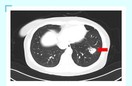

唐明副院长带领急诊科二病区医护人员进行示范查房,为患者查体听诊细致入微,充分了解患者病情进展变化。老年男性患者有高血压、糖尿病、冠心病、脑梗塞等多种基础病,且长期卧床,入院时发热,咳喘,意识不清,给予退热、抗感染、平喘等治疗后,意识转清,咳嗽,咳痰较前好转,体温一度正常,后再次出现发热。“导致患者病情变化的主要矛盾是什么?如何从检验指标中综合评价患者的营养状态?长期卧床患者三大注意事项……”唐明副院长根据患者病情对医师进行细致地考核,深入讲解进行补充指导,并根据患者个体情况,指出加强营养支持治疗的必要性。